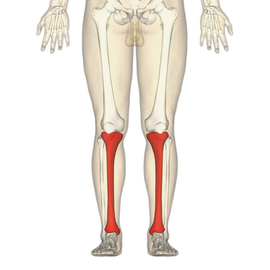

Tibia

The tibia, also known as the shinbone, shankbone or simply the shin, is the larger, stronger, and anterior of the two bones in the leg below the knee in... Wikipedia

The tibia, also known as the shinbone, shankbone or simply the shin, is the larger, stronger, and anterior of the two bones in the leg below the knee in... Wikipedia